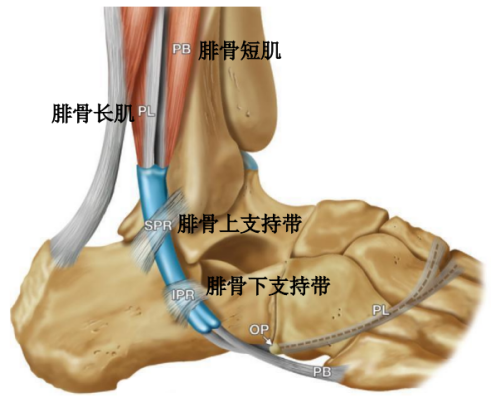

腓骨长短肌位于小腿外侧间隔。

腓骨长肌(PL):起于腓骨头、腓骨外侧面上2/3和小腿深筋膜,止于第1跖骨外侧及毗邻的第1楔骨的内侧,至小腿下1/3处,长肌移行为肌腱,在它到达止点前的行程中有三个弯曲,第一个在外踝顶点,第二个在跟骨外侧壁的腓骨肌滑车下,第三个在骰骨结节处经90°转到足底。

腓骨短肌(PB):起于腓骨外侧面下2/3及前后肌间隔,短肌至外踝的后下方始为移行为肌腱,紧贴于外踝后方,通过外踝顶点转向足外侧前方,经过跟骨外侧壁腓骨肌滑车上方最后止于第五跖骨基底。

腓骨肌腱鞘:起于外踝顶点上3.5cm并向远端延伸4cm,在腓骨的远端,腱鞘分为两部分,腓骨长、短肌腱各自进入独立的滑液鞘。

腓骨肌支持带:

腓骨上支持带(SPR):起于腓骨外侧面和腓骨外踝窝,绕过腓骨肌腱后止于跟骨和跟腱外侧。SPR没有直接牢固固定于纤维软骨脊,而是与腓骨外侧面的骨膜融合。

下支持带(IPR):前上方与伸肌支持带外侧根延续,后下方附着于跟骨前部外侧面。在跟骨滑车上下形成两个纤维管道固定肌腱于跟骨外侧壁。